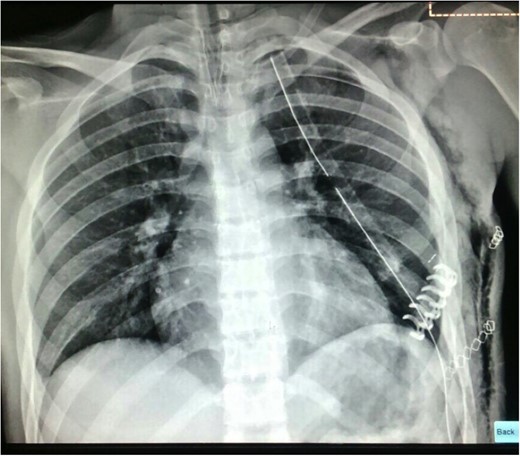

The chest CT showed moderate hemothorax, pneumothorax, a displaced fracture of the fifth left rib, and protrusion of a lung segment through a chest wall defect (Fig. 1).